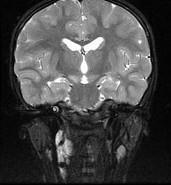

问题 女,13岁,皮肤有多发结节和多发棕色素斑,MR表现如图,最可能的诊断是()

选项 A.脸颜面血管瘤病 B.结节性硬化 C.神经纤维瘤病 D.听神经瘤 E.松果体瘤

答案 C